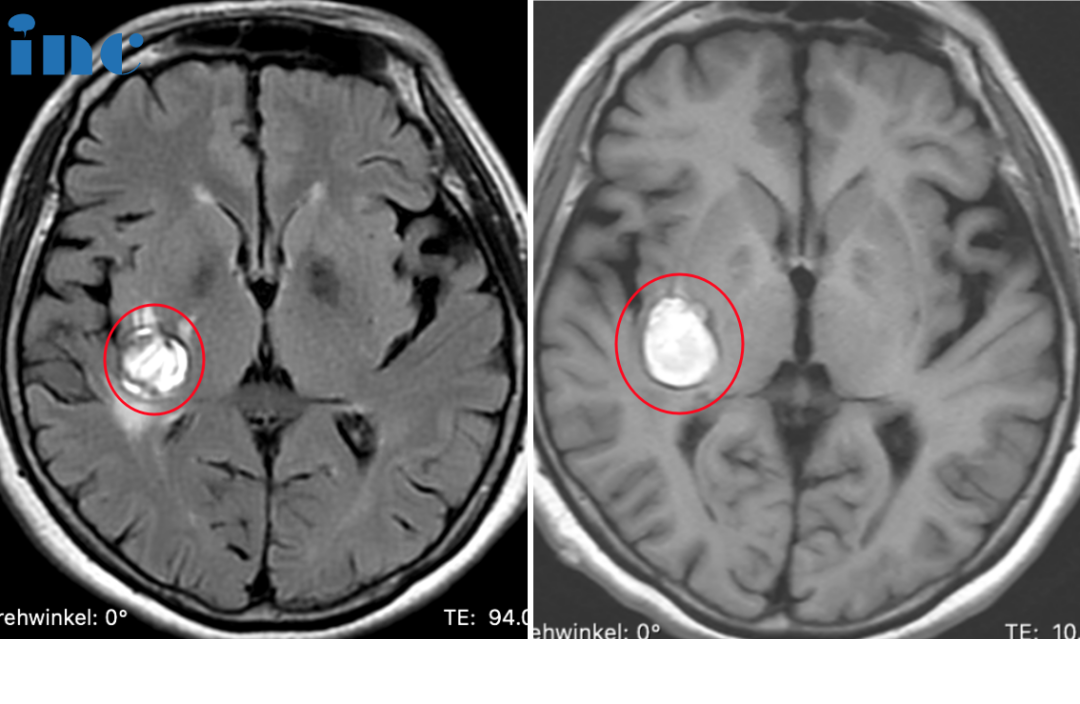

04、10岁男孩,双侧丘脑占位-胶质瘤需要手术吗?

病史摘要:2022年4月1日,涛涛因头部受伤进行头颅CT检查,结果是头部有钙化灶。7月15日,父母带涛涛到医院查头颅MRI平扫+增强,诊断结果是双侧丘脑胶质瘤可能。7月26日,再次到医院查头颅MR波谱成像(MRS),诊断结果是右侧丘脑恶性肿瘤。随后又到北京某医院问诊说可以手术,但是无法全切,且手术风险很大。涛涛目前还没有明显的症状,只是偶尔在走路的时候会突然绊一下。如果手术后,孩子变得比现在状态更差,涛涛父母犹豫了。手术还是不手术,他们多方打听之下,决定咨询国际颅底脑干手术教授巴特朗菲教授,想要听听他的意见。

INC巴教授远程评估意见:

对比2022年和的影像,我监测不到肿瘤有任何生长,很明显这是一个钙化的低级别胶质瘤。CT扫描很好地显示了右侧肿瘤内的强化的钙化。

在这种情况下,特别是考虑到这个男孩的临床状况良好,我们可以通过反复的核磁共振成像检查对他的病例进行跟踪,因此,如果出现任何变化,我们都可以很容易地发现。

不过,这种肿瘤很有可能在多年内保持稳定,而且,在接下来的几年里,当男孩继续生长时,肿瘤甚至可能出现退化(肿瘤体积可以在不治疗的情况下缩小)。当然,这只是一种可能性,我们当然不能确定这种有利的发展过程是否真的会发生,但至少有很大的机会出现这种有利的情况。

至于体重增加,也许是因为下丘脑也受累了,因为下丘脑与丘脑紧密相连,也许也含有小部分肿瘤。因此,男孩需接受儿科肿瘤专家的诊治,检查全部(下丘脑相关的)激素,并根据具体情况替代激素。不过,要阻止下丘脑肿瘤引起的体重增加并不容易,因为目前还没有合适的药物。